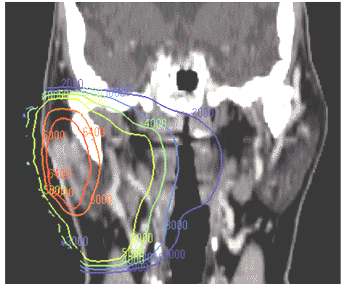

Treatment (according to the NCI): "The minimum therapy for low-grade malignancies of the superficial portion of the parotid gland is a superficial parotidectomy. For all other lesions, a total parotidectomy is often indicated. There is growing evidence that postoperative radiation therapy does augment surgical resection, particularly for the high-grade neoplasms, or when margins are close or involved." See typical radiation techniques with either mixed beam or wedged pairport around tumor, typical radiation port

Radiation was delivered through an ipsilateral field of predominantly high energy electrons in 142 patients (86%). Wedged paired 60Co fields were used to treat 19 patients. The median dose was 60 Gy, typically delivered at 2 Gy per fraction. The median follow-up time for surviving patients was 155 months. RESULTS: Forty-seven (29%) patients had disease recurrence, of whom 15 (9%) had disease recur locally and 10 (6%) regionally (neck). There was no association between the dose of radiation and local failure, except for a trend for patients with positive margins and/or named nerve involvement to have improved local control if they received doses > 60 Gy. There was no difference in failure rates in patients treated with wedged pair techniques or ipsilateral fields, but there was a higher complication rate in the former. Overall, 37 patients (22%) developed chronic sequelae attributed to radiation. Twelve patients developed decreased hearing, and 15 patients developed soft tissue or bone necrosis or exposure. CONCLUSIONS: Local and regional control rates for high risk patients with parotid gland carcinomas treated with radiation following surgery were excellent. The technique of using an ipsilateral field encompassing the parotid bed and treated with high energy electrons often mixed with photons was effective with minimal severe late toxicity. The moderate complication rate experienced in this series can be further reduced using modern techniques as described.